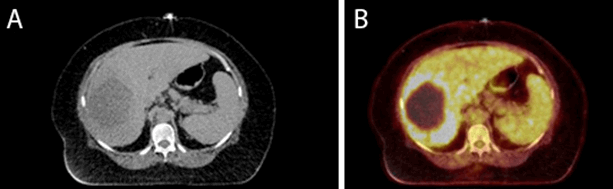

The patient underwent endoscopic ultrasound (EUS), Gallium 68-DOTATATE positron emission tomography (PET, due to initial pathologic diagnosis of neuroendocrine tumor), whole-body nuclear medicine (NM) PET, magnetic resonance (MR) scan of the abdomen, chest CT, and mammogram that revealed no other lesions and no pancreatic tumor. The patient’s nodules were originally diagnosed as erythema nodosum by her dermatologist and treated with an ineffective six-day course of topical steroids. Lab values were notable for marked hyperlipasemia (>14,000 U/L, normal <50 U/L) upon presentation, white blood cell count of 13,900/µL (normal <10,000/µL) without eosinophilia, hemoglobin 9.9 g/dL (normal 12–16 g/dL). Liver function tests and tumor markers (AFP, CEA) were AST 28, ALT 18, ALP 168, total bilirubin 0.3, CEA <1, AFP <2, CA 19-9 <2. The remaining parameters were within normal limits. FDG PET scan of the whole body demonstrated the large liver lesion with no FDG-avid lymph nodes or metastases three days before the date of surgery (Figure 2).

Figure 2. Preoperative imaging: nuclear medicine positron emission topography (PET) scan demonstrating 9.6 cm necrotic lesion in the right lobe of the liver, segment 6/7; A) represents the scan without tracer; and B) demonstrates decreased fluoro-deoxyglucose (FDG) uptake in the area of the lesion compared to the surrounding liver, with a thick irregular rim of hypermetabolic activity—no extrahepatic lesions were noted